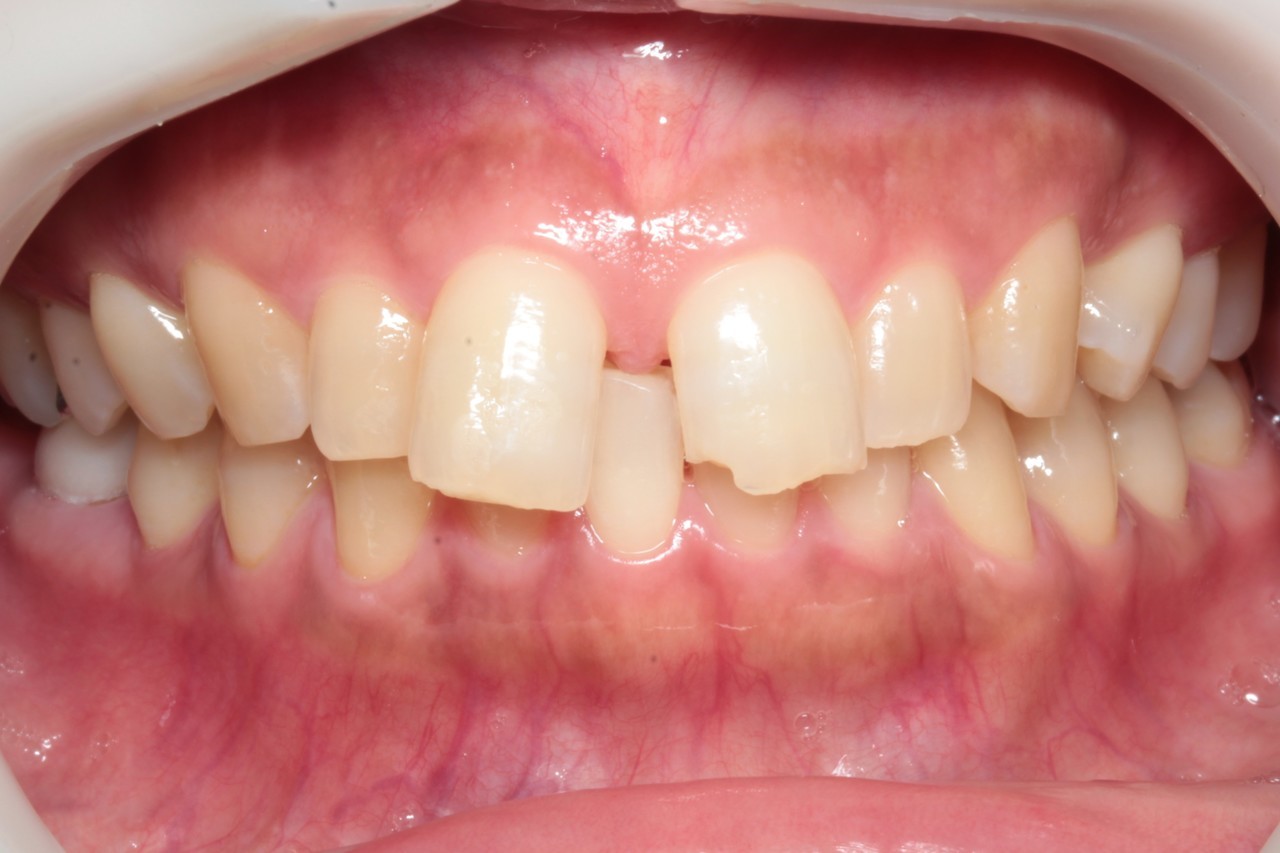

治療前

調布市の30代女性

主訴:歯と歯の間のすきまが気になる

使用装置:インビザライン

治療期間:約1.5年

治療費用:93.5万円(税込)

治療結果:空隙歯列が改善されました

※治療前の欠けている前歯は治療後に当院で修復しております

①の症例よりも前歯の離開度合いが強く

更に前歯が下方に挺出(ていしゅつ:歯の飛び出しのこと)しているので

圧下(あっか:歯を押し込むこと)をしっかり行うことが仕上がりに大きく影響します

また上の歯を配置するにあたり、下の歯も圧下する必要がありました

この上下の圧下が一番のポイントとなります